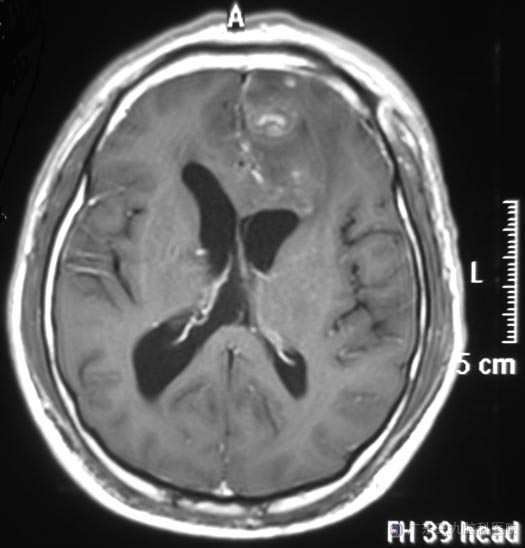

这天早晨八点左右,家人发现他进了卫生间后好久都没有出来,撬开门,发现高先生晕厥在里面。“120”急送当地医院,当时他双侧面部潮红,小便失禁,约一小时后神志清醒,不能回忆,没有不适感觉。头颅CT检查提示:左侧前颅窝占位;广东三九脑科医院头颅MR检查提示左侧额部镰旁占位,大小约54.5mm×68.6mm×55.1mm,邻近双侧侧脑室、胼胝体及脑组织明显受压,综合神经外科 鲁明主任初步考虑为脑膜瘤。

完善术前准备后,鲁明主任主刀,在全麻下行左侧额部大脑镰旁脑膜瘤切除术,显微镜下见肿瘤呈肉红色,质软,血供丰富,边界清楚,完整切除肿瘤,嗅神经、双侧大脑前及骈周动脉保留完好。术后高先生很快康复。病理结果为:过渡型脑膜瘤(WHO I级)。